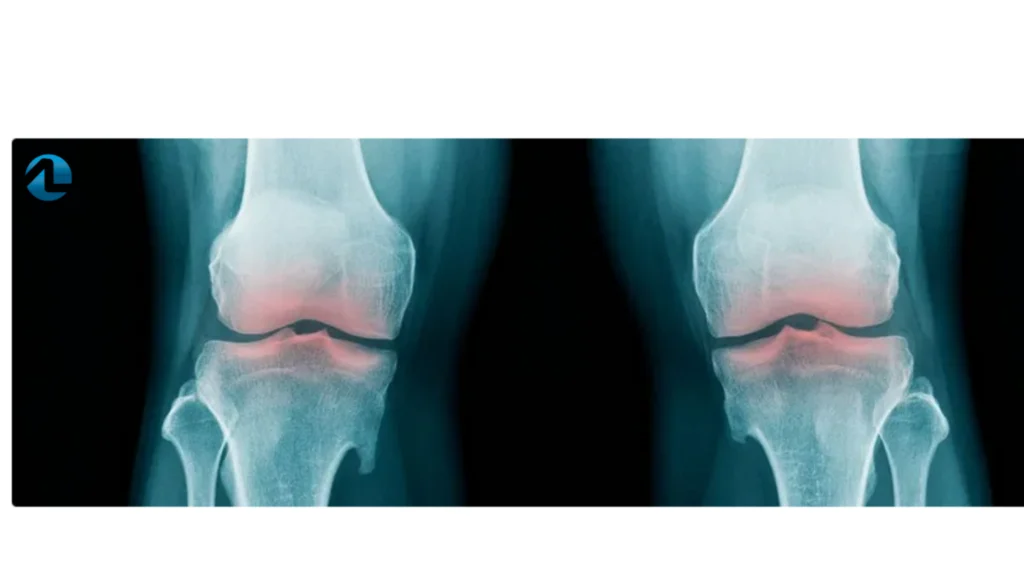

Um estudo de 2015 na revista Public Library of Science One, avaliou a ingestão diária de magnésio e a osteoartrite avaliando por meio da mudança na radiografia do joelho desses pacientes. Notou-se estreitamento do espaço articular e diminuiu os esporões ósseos.